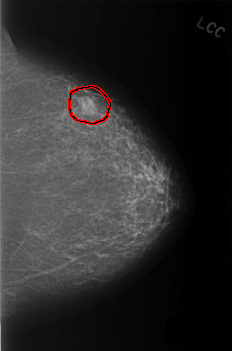

C_0331_1.LEFT_CC

FILE: C_0331_1.LEFT_CC.OVERLAY

TOTAL_ABNORMALITIES 1

ABNORMALITY 1

LESION_TYPE MASS SHAPE LOBULATED MARGINS OBSCURED

ASSESSMENT 3

SUBTLETY 5

PATHOLOGY BENIGN

TOTAL_OUTLINES 1

BOUNDARY